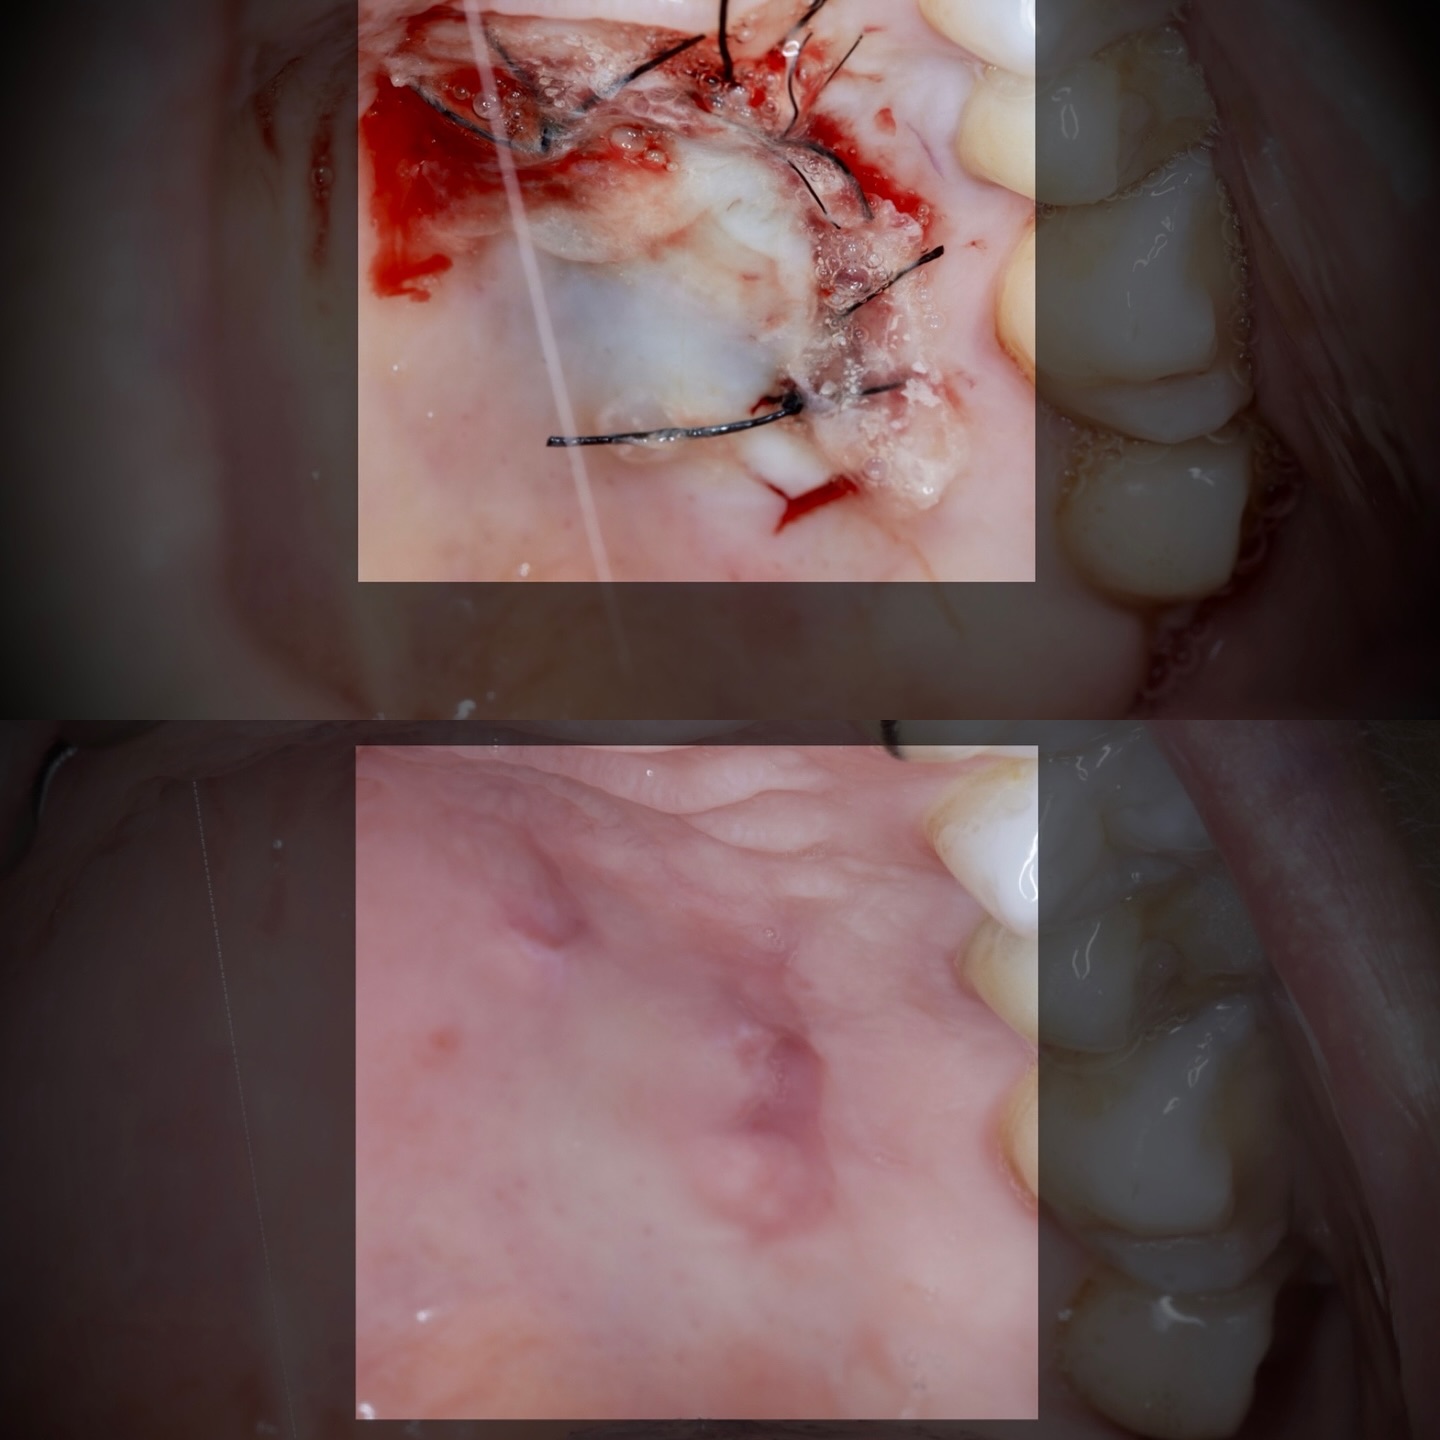

Podrás asistir a la planificación de casos y cirugía de injerto de tejido conectivo. Factores determinantes y elección de la técnica adecuada. Sumérgete en un protocolo predecible y técnicamente correcto para obtener resultados óptimos.

Se realizará todo el procedimiento con un microscopio operatorio, lo que permite al alumno ver toda la cirugía en directo en una pantalla en la sala de cirugía.

Una estancia clínica pensada para quienes quieran iniciarse o dar un paso más en el campo de la cirugía mucogingival. Durante esta experiencia tendrás la oportunidad de aprender en directo cómo se planifica y se lleva a cabo una cirugía mucogingival mediante técnica de Túnel.

La sesión